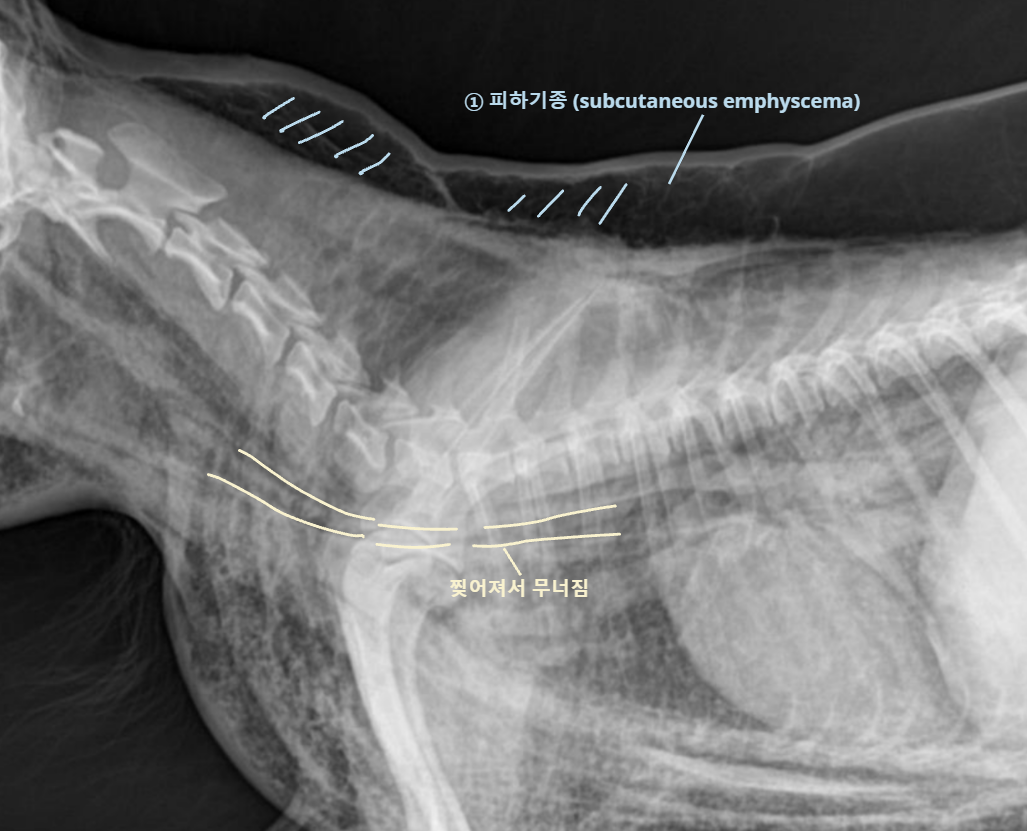

Tracheal rupture